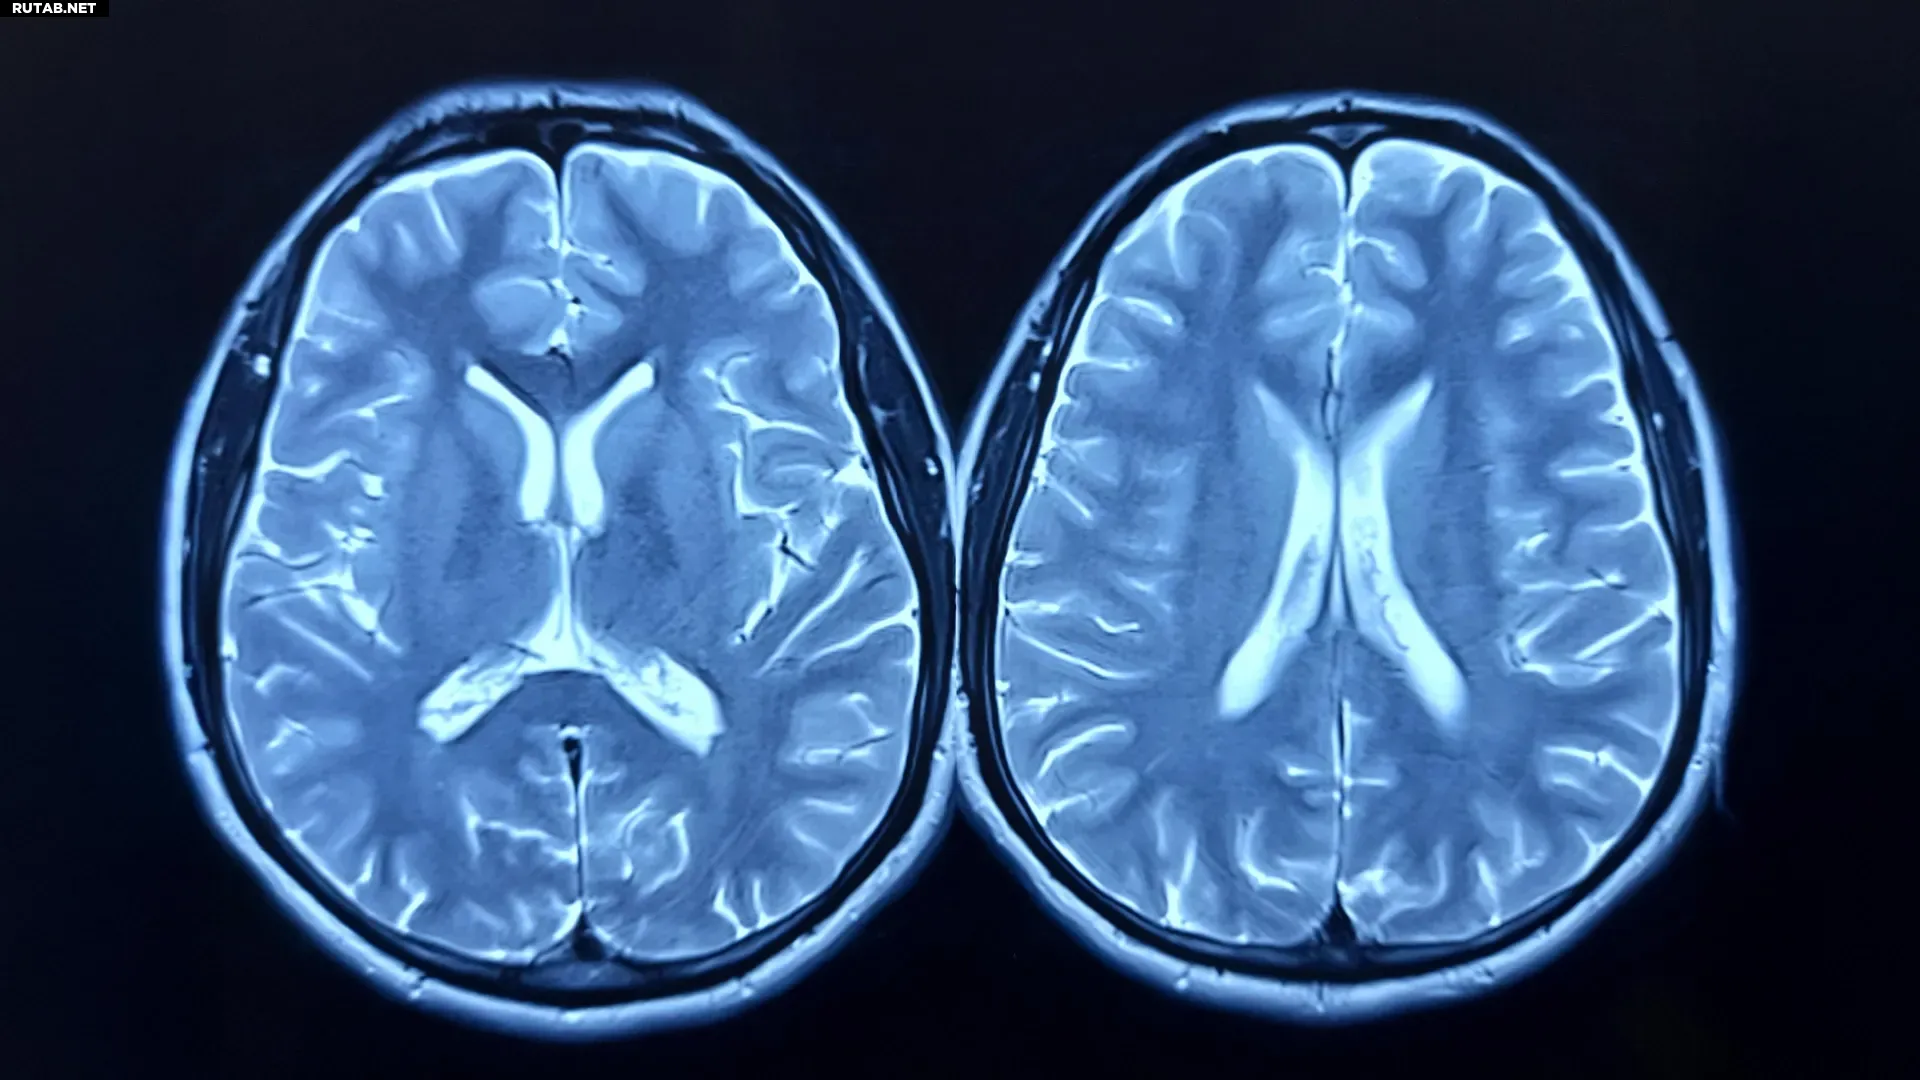

В клиническом испытании участвовали 130 здоровых взрослых. Одни в течение года следовали рекомендациям Американского колледжа спортивной медицины (около 150 минут аэробной активности в неделю), другие вели привычный образ жизни. Структуру мозга оценивали с помощью МРТ-сканирования в начале и через 12 месяцев.